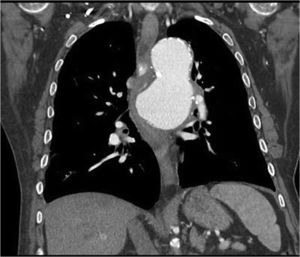

Sixty-four-year-old male with a history of thoracic aortic aneurysm who came to the emergency department due to the feeling of blockage at mid-oesophageal level which led to vomiting after eating. He denied bolus obstruction. He reported the presence of strands of blood in the most recent vomiting, as well as dyspnoea and orthopnoea. A chest X-ray showed an increase in the size of the aortic aneurysm, which led to a CT-angiogram being performed, showing hyperdense content in the oesophageal lumen, as well as signs of instability and penetrating ulcer which was in contact with and compressed the oesophageal lumen and the left bronchus (Figs. 1 and 2). Urgent surgery was performed with the fitting of an aortic stent, with no immediate complications. At 48h, the patients presented with haematemesis, with gastroscopy showing a mid-oesophageal clot and pulsating bleeding. In view of a suspected endoleak a surgical review was performed, with the arteriography showing no periprosthetic leakage. The patient presented with haemodynamic shock which did not respond to multiple transfusions or vasoactive drugs, leading to death. In the autopsy, the presence of an aortoesophageal fistula was confirmed (Fig. 3).

Oesophageal dysphagia secondary to extrinsic vascular compression is a rare cause of dysphagia, with the presence of cardiovascular abnormalities being the most common cause.1 Aortic dysphagia refers to dysphagia brought about by atherosclerosis or aortic aneurysm.2 Clinical manifestations of dysphagia and upper gastrointestinal haemorrhage may appear in complicated aneurysms, as in the case of our patient, with secondary aortoesophageal fistula being a complication with high mortality.3